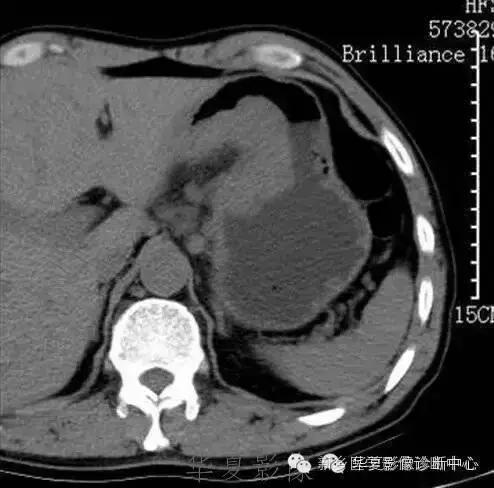

肝脏黑色素瘤

原发于肝脏的恶性黑色素瘤极其罕见。肝脏原发恶性黑色素瘤临床表现及体征均无特征性,与其他肝脏占位性、 肿瘤性病变无法区分,此为该病的临床特征。

肝脏恶性黑色素瘤的超声和 CT多表现为肝脏增大,肝内单发、 多发占位病变或弥漫性、 结节性改变, 占位性病变可为实性、 囊性、 囊实性改变,但上述改变无明显特异性, 与其他肝脏恶性肿瘤无法区分。MR T1 加权呈高信号、 T2 加权呈低信号